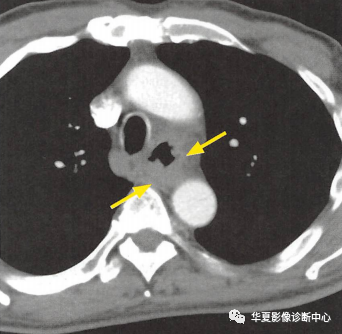

(上圖:增強(qiáng)CT食管壁不規(guī)則增厚)